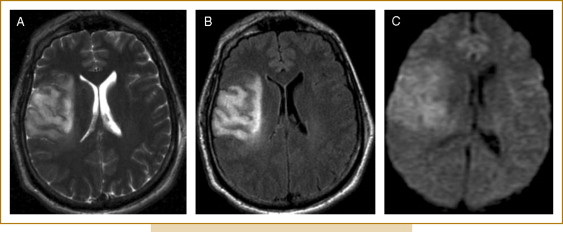

1. 신속한 평가 및 진단: 뇌경색 초기증상과 징후를 신속하게 인식하는 것은 적시에 개입하고 환자 결과를 개선하는 데 필수적입니다. 의료 전문가는 NIHSS(National Institutes of Health Stroke Scale)와 같은 도구를 사용하여 잠재적인 뇌경색 환자를 신속하게 평가하고 컴퓨터 단층 촬영(CT) 스캔 또는 자기 공명 영상(MRI)을 포함한 진단 테스트를 시작하여 진단을 확인하고 유형을 결정해야 합니다.